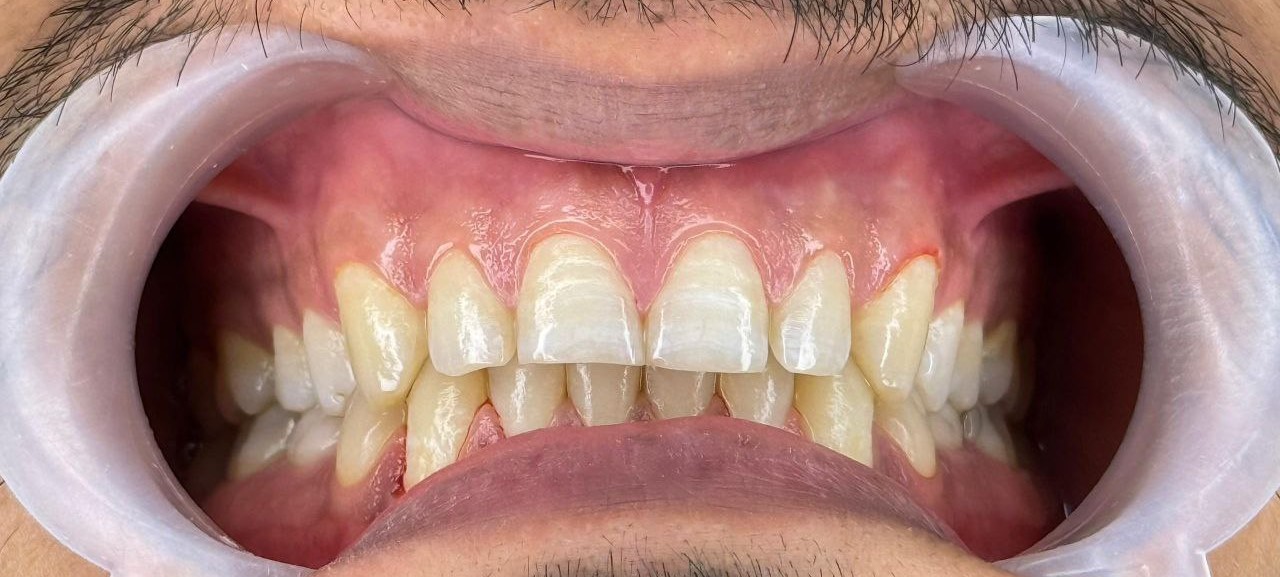

قبل و بعد لیمینت

قبل و بعد لیمینت

قبل و بعد لیمینت

قبل و بعد لیمینت